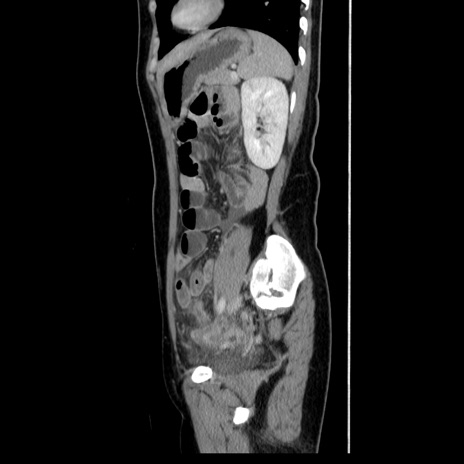

症例39(矢状断像)

【症例】40歳代女性

【主訴】上下腹部痛

【現病歴】2日目から下腹部痛あり。夜間は痛みで眠れなかった。昨日より上腹部痛と下痢が出現。臥位で痛みは軽快したため、休んでいた。本日になって臥位でも立位でも痛みが強くなってきたため救急要請。

【既往歴】子宮内膜症

【身体所見】部:平坦・軟、左上下腹部に圧痛あり、反跳痛あり。

【データ】WBC 21800、CRP 26.78

CT